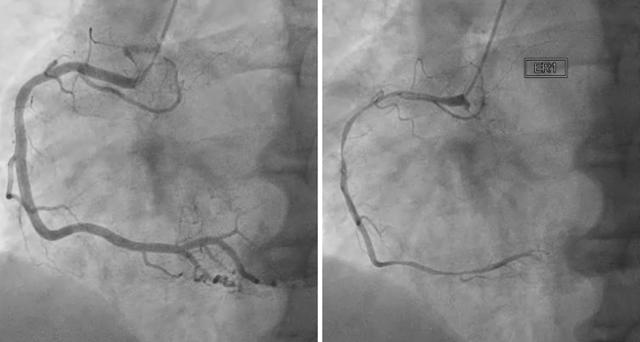

치료는 원인을 제거하는 방법인데 혈관을 넓혀주는 방법이죠. 심하지 않다면 약물 치료를 통해 호전이 될 수 있지만 그와 반대로 심한 경우에는 수술이 필요할 수 있다고 합니다. 혈관을 넓혀주는 방법이며 스텐트 삽입술, 응급 심혈관성형술 등이 있다고 해요. 쉽게 설명하자면 혈관에 관을 삽입해서 인위적으로 넓혀주는 것입니다 가운데가 뚫린 관을 혈관이 좁은 곳에 넣는 것인데요.